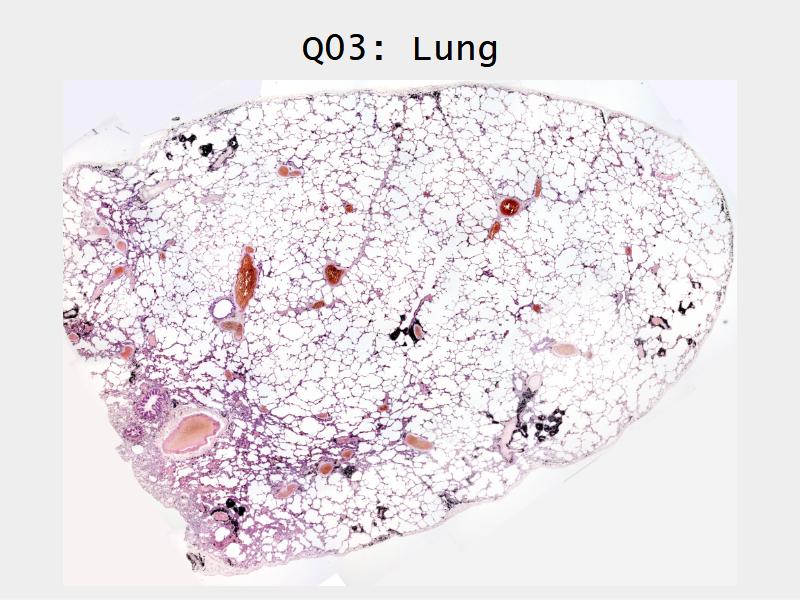

Slides: Respiratory System

- Slide 72 & 74: Lung

Lungs